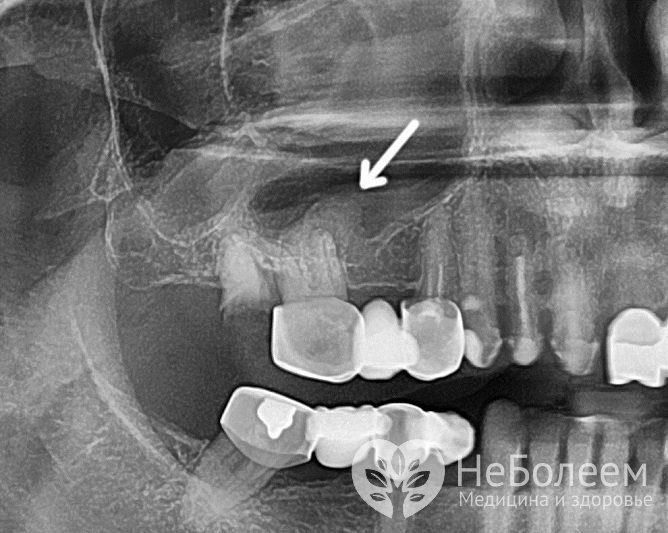

Для диагностики болезни назначается рентгенологическое исследованиеРентгенологическое исследование проводится в нескольких проекциях. На фото (рентгенограмме) определяется гомогенное затемнение пазухи, утолщение слизистой оболочки за счет отека. На произведенном в вертикальном положении снимке гной выглядит в виде уровня жидкости.